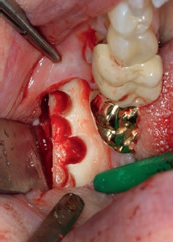

In Lokalanästhesie wurde mit einer vertikalen Entlastung an Zahn 24 und einer marginalen Schnittführung 25, welche mittig im Bereich der Linea alba nach distal fortgeführt wurde, ein Mukoperiostlappen gebildet. Der dreidimensionale Defekt wurde mit einer Präparation nach palatinal dargestellt und das Titangitter auf seine Passform kontrolliert. Bereits zum jetzigen Zeitpunkt erfolgte eine Periostschlitzung für einen späteren spannungsfreien Wundverschluss. Nach Ausdünnung des Knochenfensters mit dem Safescraper wurde das bukkale Fenster für den externen Sinuslift präpariert und die Schneider-Membran angehoben. Diese zeigte sich als vollständig intakt. Aufgrund des großen Augmentationsvolumens wurde zusätzlich retromolar in regio 47/48 mit einem Trepanbohrer autologer Knochen entnommen (Abb. 2) und mit einer Knochenmühle in kleine Knochenspäne zerkleinert. Das Mischverhältnis im Bereich der Augmentation lag bei einem Anteil von 50% autologem Knochen mit 50% bovinem Knochenersatzmaterial (Bio-Oss, Geistlich) (Abb. 3), wobei im Bereich der Kieferhöhle mit etwas mehr DBBM und nur einer geringeren Menge an autologen Knochenchips gearbeitet wurde. Nach dem Auffüllen des Sinus (Abb. 4) wurde das individuelle Titangitter mit leicht rüttelnden Bewegungen auf den Defekt gesetzt und dessen Passform an den Füßchen am Rande des Gitters überprüft. Anschließend wurde es mit 2 Osteosyntheseschrauben lagestabil fixiert (ADS Schrauben, American Dental) (Abb. 5) und zusätzlich mit einer Kollagenmembran abgedeckt (Biogide, Geistlich) (Abb. 6). Es erfolgte ein primärer Wundverschluss mit 2 tiefen Matratzennähten und einer fortlaufenden Naht (Seralon 5/0, Serag-Wiessner) (Abb. 7). Postoperativ wurde die Patientin gebeten, für 2 Wochen das Schnäuzen der Nase zu unterlassen.